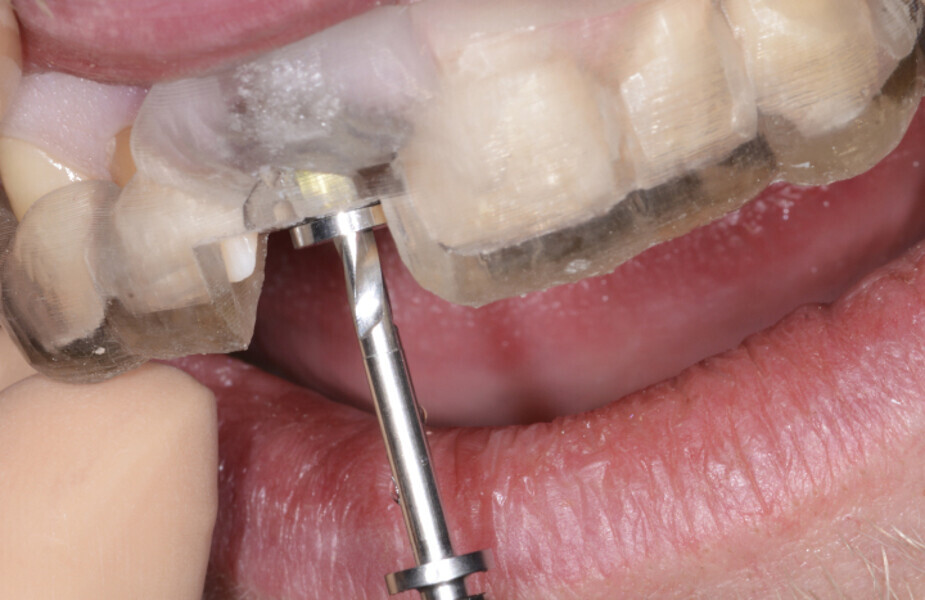

Fig. 14: A sequence of implant drills with specific guide sleeves were used.